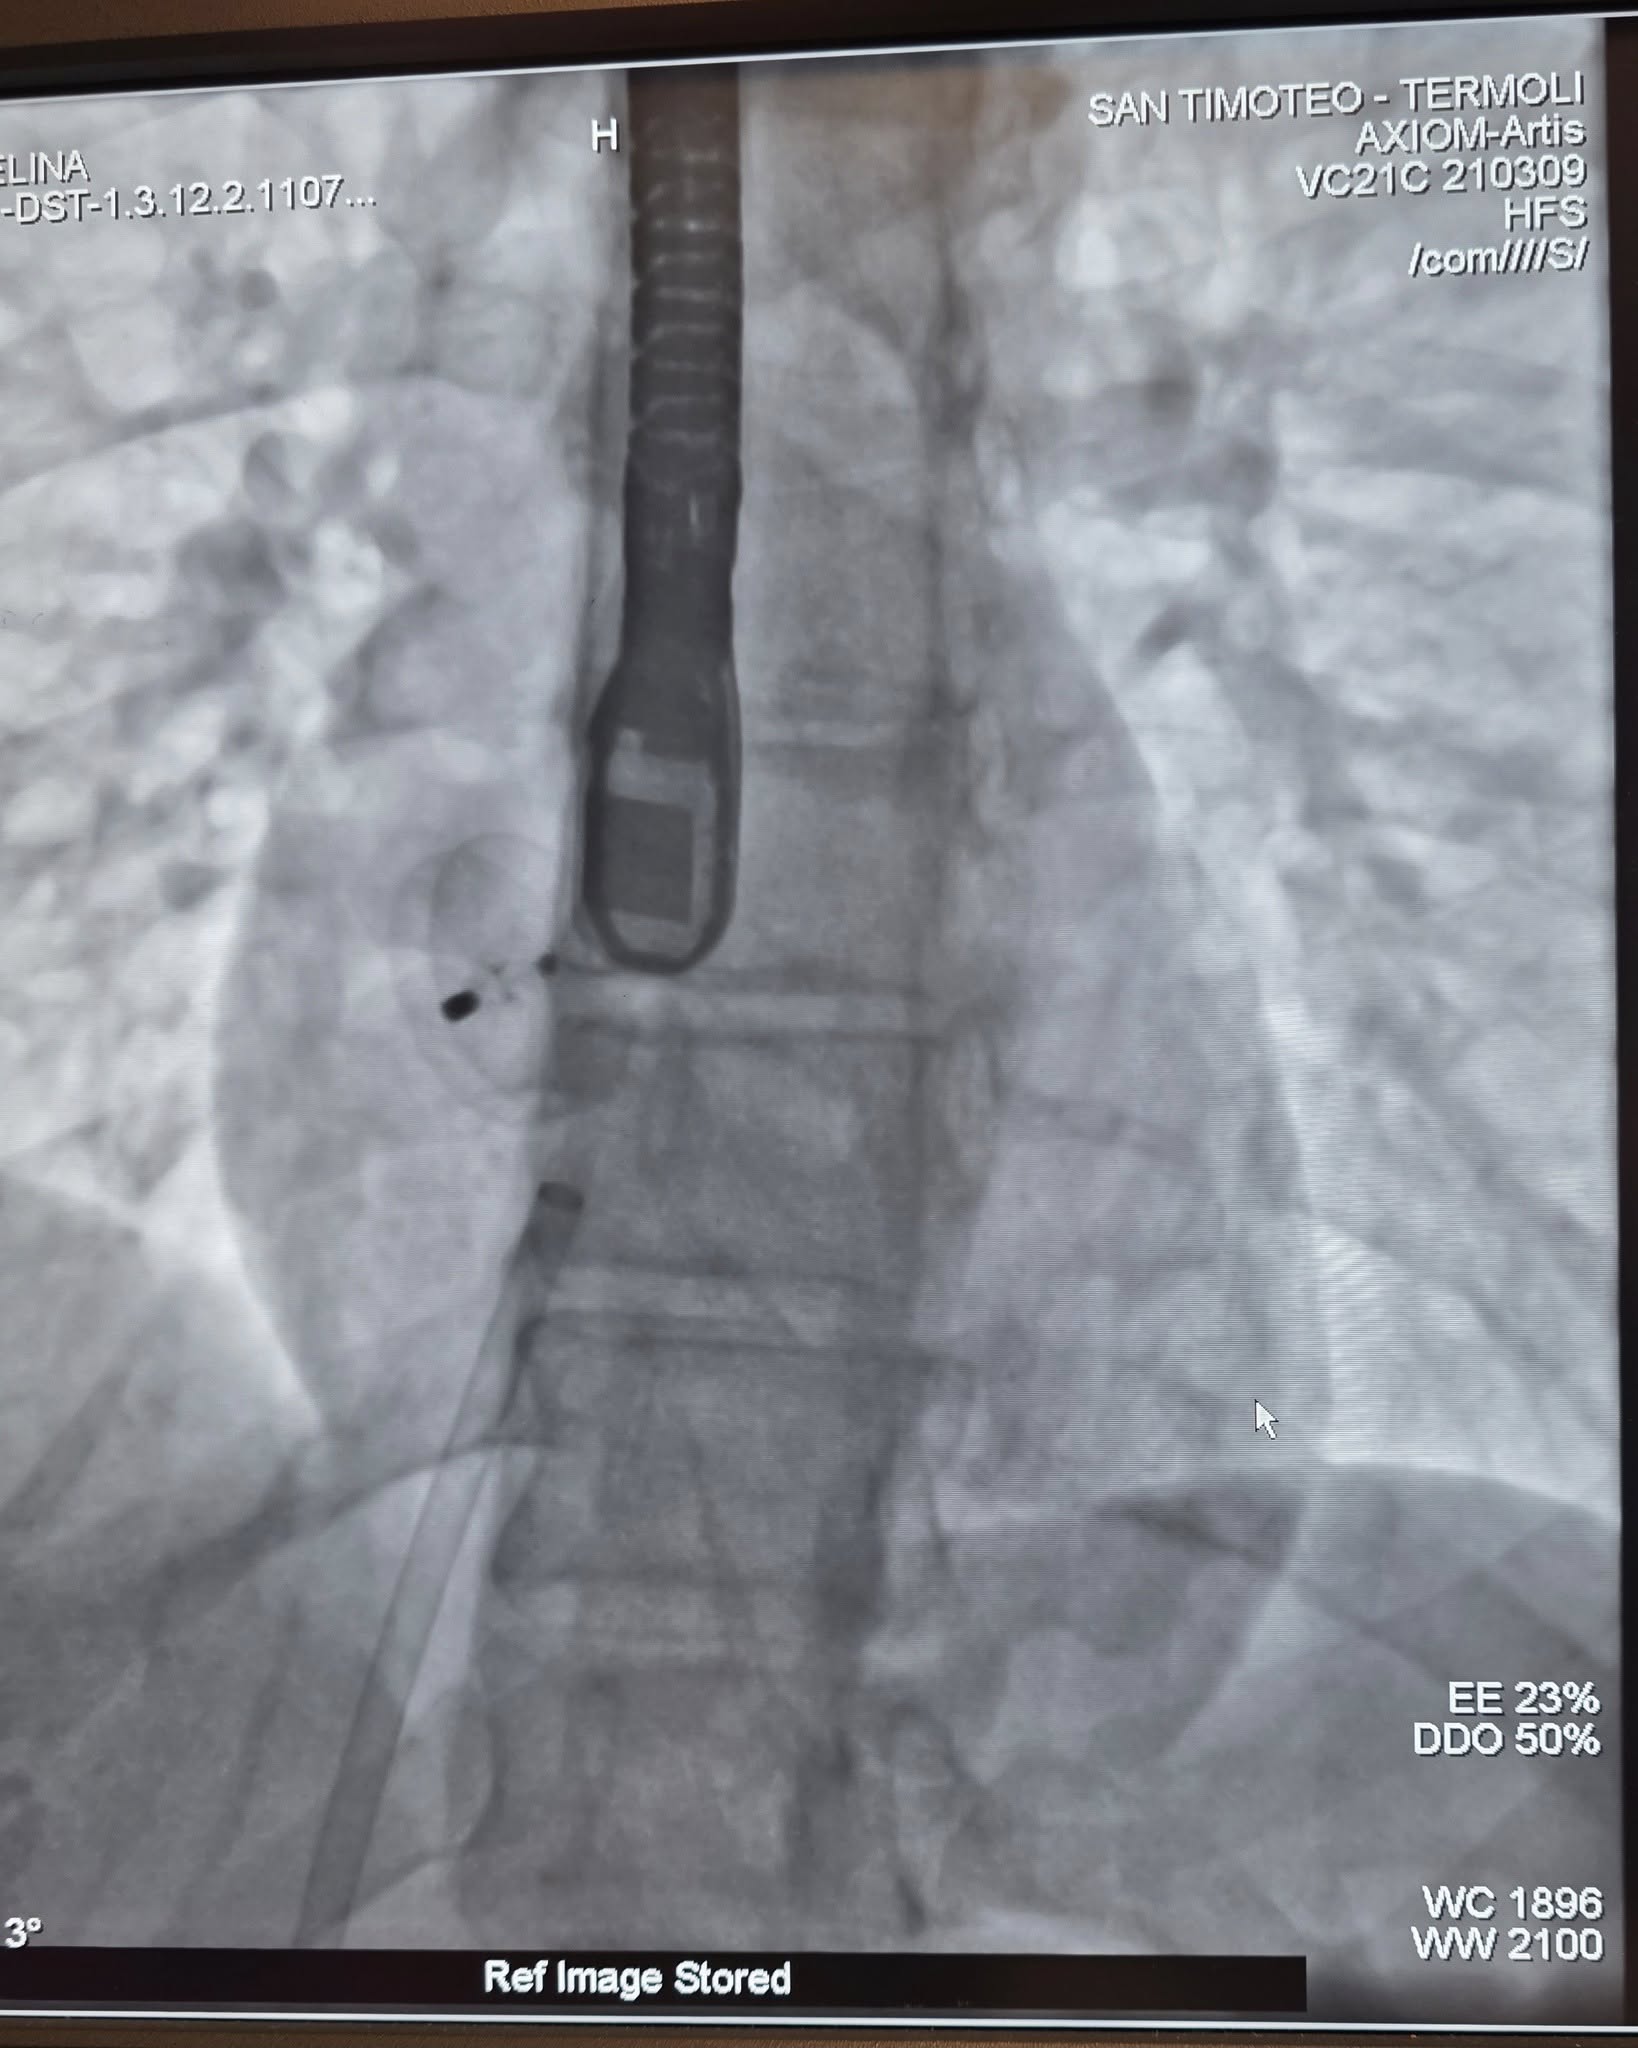

Si tratta di interventi mini-invasivi che mirano a chiudere una comunicazione anomala tra i due atri del cuore, spesso identificata come un’apertura residua del forame ovale presente nel periodo fetale. Si eseguono mediante l’introduzione di un dispositivo, simile a un ombrellino, attraverso un catetere, generalmente introdotto attraverso la vena femorale.

“Le procedure – ha commentato il dott. Gianludovico Magri, Direttore della SC di Cardiologia del San Timoteo -si sono concluse con successo e senza complicanze. Stiamo rispondendo alle esigenze di certezza e sicurezza delle cure dei pazienti con meticolosa attenzione, garantendo al territorio le stesse opportunità di altre realtà. Tutto questo è possibile grazie all’instancabile équipe di Emodinamica, a tutti i medici, gli infermieri gli OSS dell’ospedale di Termoli, ai quali sto chiedendo tanti sacrifici, e alla macchina organizzativa dell’ASReM, che si è attivata a monte per poter raggiungere questo risultato!”